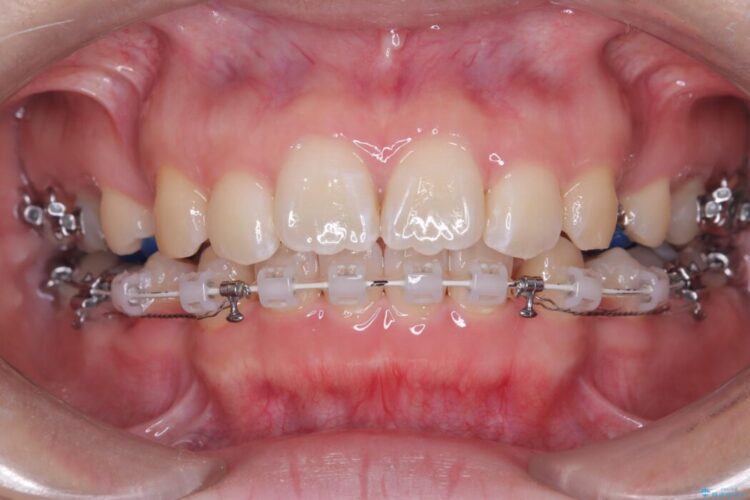

装置は人目を気にせず治療できるよう、上顎に裏側矯正、下顎に表側矯正を組み合わせたハーフリンガル矯正を提案しました。

装置には、上顎には目立たない裏側矯正(舌側矯正)を、下顎には透明な審美ブラケットを使用するハーフリンガル矯正を採用しました。抜歯によってできたスペースを最大限に活用し、前歯を効率よく後方へ移動。治療の結果、口元の突出感が大幅に解消され、Eライン(横顔の美しさの基準)も改善しました。人目を気にすることなく治療を完遂し、自信の持てる美しい横顔を獲得していただけました。